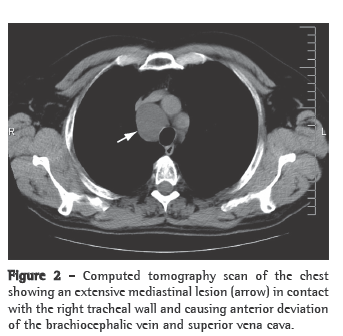

A 50-year-old male smoker (30 pack-years), a car salesman with a history of arterial hypertension and dyslipidemia, sought medical attention. The patient was under regular treatment with simvastatin (20 mg), valsartan (80 mg), lansoprazole (30 mg), and brotizolam (0.25 mg). The patient was referred to a pulmonologist due to the finding of right paratracheal lesion with enlargement of the upper mediastinum on a routine chest X-ray (Figure 1).

The presumed diagnosis is made based on the detection of a cystic lesion on a chest X-ray or a computed tomography scan of the chest.(5) On X-rays, lymphangiomas of the mediastinum appear as well-circumscribed, round masses of homogeneous density,(5) and computed tomography of the chest demonstrates the involvement or deviation of natural structures, absence of calcification, and various high attenuation areas within the lesion.(2)